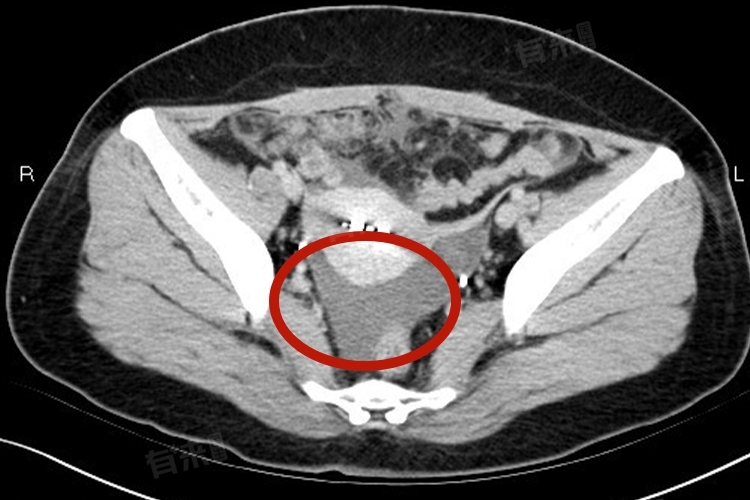

盆腔积液能否怀上孩子需综合多方面因素判断,积液量的多少、有无伴随症状以及是否积极治疗等都起着关键作用。

1、积液量的多少:如果盆腔积液量较少,可能是生理性的,女性在月经期或排卵期,盆腔内会有少量的组织液渗出积聚形成积液,生理性的盆腔积液一般不会对怀孕造成直接影响,因为产生是身体正常生理过程的一部分,不会干扰到生殖系统的正常功能,如卵子的排出、输卵管的通畅以及受精卵的着床等基本生殖环节。